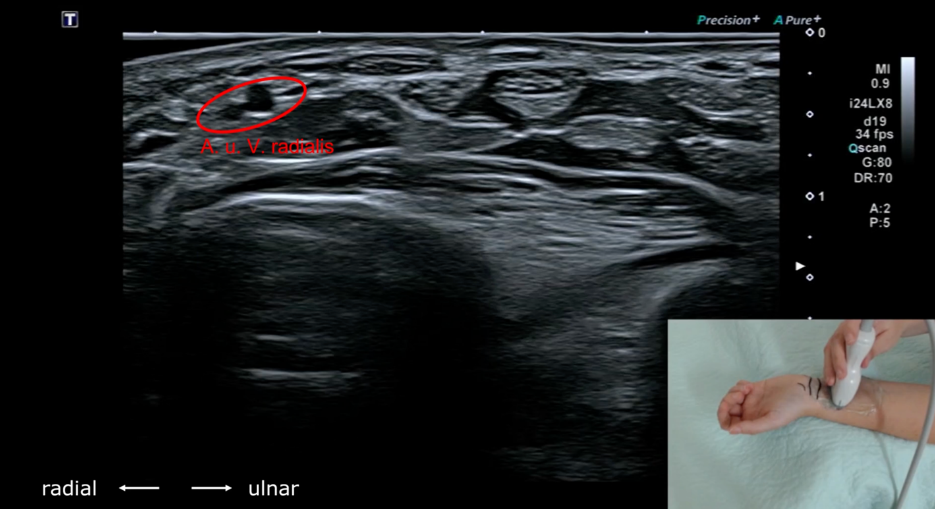

Grundkurs Nervenultraschall -

Nervus medianus

Dieses Tutorial richtet sich vor allem an Anfänger und soll euch einen kurzen Überblick über die Sonoanatomie sowie die wichtigsten Messpunkte des Nervus medianus zur Diagnostik des Karpaltunnelsyndroms geben.